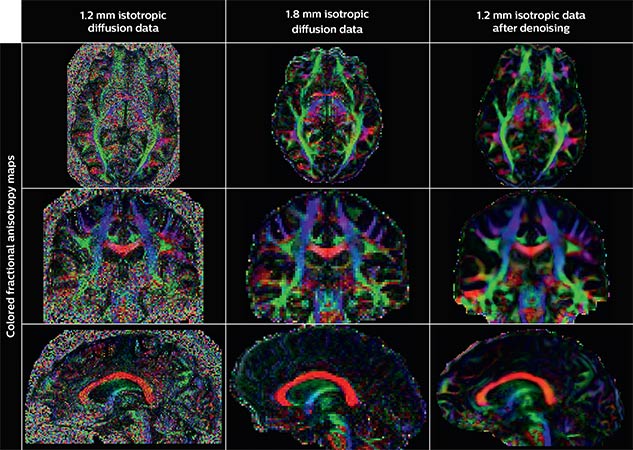

Denoising to improve quality

Using a non-local spatial and angular block matching technique to denoise raw diffusion weighted images. allows to push acquisition to lower spatial resolution and read human-connectome-project-like resolution from standard Philips Ingenia 3.0T MRI scanner. The data were acquired with spatial resolution of 1.2 x 1.2 x 1.2 mm in 13 minutes for 40 full brain DWI with b 1000 and one with b 0